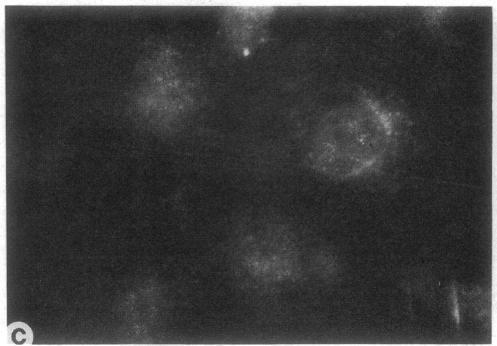

Cells from patients with peroxisome-deficient disorders contain membrane ghosts devoid of most matrix contents instead of normal peroxisomes indicating that the underlying molecular defects impair the import of matrix proteins into these peroxisome ghosts. Genetic heterogeneity for the molecular defects was inferred from the assignment of patients with peroxisome-deficient disorders into nine complementation groups. The aim of our studies was to analyze cell lines from six different complementation groups in a systematic manner for the presence of peroxisome ghosts, the ability to import Ser-Lys-Leu-containing proteins into peroxisome ghosts and for the presence of cytosolic factors required for peroxisomal protein import. We show that each of the cell lines analyzed contains peroxisome ghosts, but is unable to import matrix proteins as judged by a peroxisomal import assay using permeabilized cells. The addition of wild type cytosol did not restore the capacity to import matrix proteins but cytosol prepared from these cell lines was functional in stimulation of peroxisomal protein import in a heterologous system. These results implicate organelle-associated molecular defects in each of the six cell lines analyzed.

过氧化物酶体缺陷症患者的细胞含有缺乏大多数基质成分的膜空壳,而非正常的过氧化物酶体,这表明潜在的分子缺陷会损害基质蛋白导入这些过氧化物酶体空壳。根据过氧化物酶体缺陷症患者被分为九个互补组,推断出分子缺陷存在遗传异质性。我们研究的目的是系统分析来自六个不同互补组的细胞系,以检测过氧化物酶体空壳的存在、将含丝氨酸-赖氨酸-亮氨酸的蛋白质导入过氧化物酶体空壳的能力以及过氧化物酶体蛋白导入所需的胞质因子的存在情况。我们发现,所分析的每个细胞系都含有过氧化物酶体空壳,但通过使用通透细胞的过氧化物酶体导入试验判断,其无法导入基质蛋白。添加野生型胞质溶胶并不能恢复导入基质蛋白的能力,但从这些细胞系制备的胞质溶胶在异源系统中对刺激过氧化物酶体蛋白导入具有功能。这些结果表明,在所分析的六个细胞系中均存在与细胞器相关的分子缺陷。